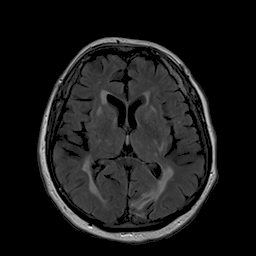

III-A Data

We analyze the performance of the proposed approach based on 21 pairs of clinical patient head datasets. First, 8 pairs of tomographic T1 and T2 Flair MRI datasets (256x 256256x256256\;\text{x}\;256) are used. Second, cone-beam X-ray and MRI projection images (512x 512512x512512\;\text{x}\;512) generated from 13 patients are utilized (MR: 1.5 T MAGNETOM Aera / CT: SOMATON Definition, Siemens Healthineers, Erlangen / Forchheim, Germany). Two pairs of patient dataset of each modality were reserved for validation and testing. Image registration of the corresponding datasets is performed using 3D Slicer [30]. The forward projections are based on the work of hybrid MR/X-ray imaging by [31, 32, 33] and are created with the CONRAD framework [34]. 108 projections are created per patient that are distributed equiangularly along the azimuthal and in 60 degree range along the inclination angle. Note that the type of data presented here is only to be seen as an example. The proposed approach is not tailored to any particular data type or combination of data types.

For the task of super resolution, low-resolution images are created by nearest neighbor downsampling by a factor of 4. For denoising, noisy images are generated from the ground truth by applying Poisson noise. Both methods are only an approximation of the real physical processes. In MRI, for example, the resolution and the signal-to-noise ratio are directly related [35]. Also, noise in X-ray imaging is not just Poisson noise but a combination of multiple sources of noise [36]. For detailed investigations on a specific problem area a corresponding simulation should therefore be conducted.

Figure 2: Inputs and outputs of the guided filtering pipeline based on the WDSR network. T1 & T2 MRI pairs (a)-(e) and CT & MRI projection images (f)-(j).